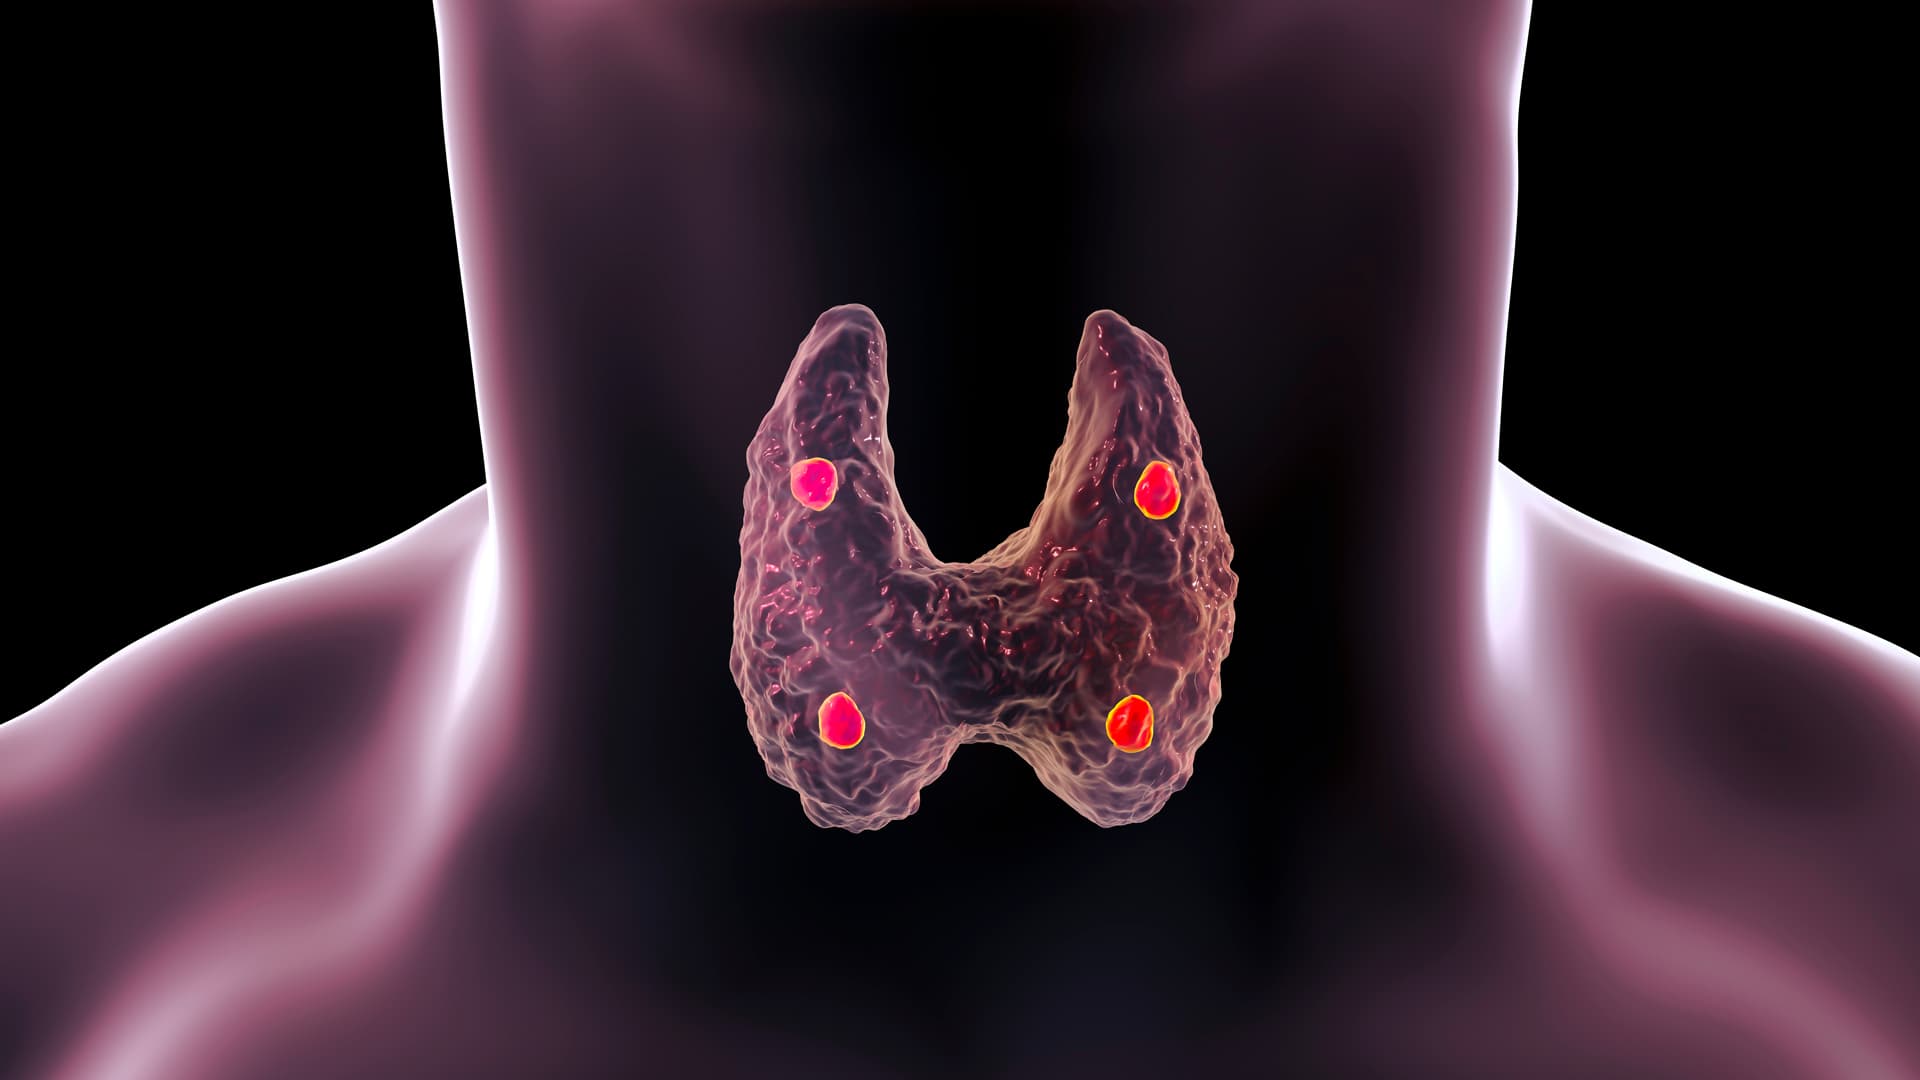

Cortisone sans ordonnance. La thyroïde synthétise les hormones thyroïdiennes.Maladies de la thyroïde : les traitements médicamenteux. Des niveaux élevés de cortisol peuvent inhiber la production de TSH et . En effet, ce médicament est un corticostéroïde qui agit . 4 - La ménopause.Press release - Posted on Mar 14 2023.Il s’agit d’un trouble inflammatoire chronique de la glande thyroïde causé par des anticorps sanguins anormaux et des globules blancs qui attaquent et endommagent les cellules thyroïdiennes.Les effets secondaires les plus fréquents de la cortisone sont liés à son action sur le système hormonal. Parfois, elle produit trop d’hormones, c’est l’hyperthyroïdie. La scintigraphie permet ainsi d’obtenir une image du fonctionnement de la thyroïde et de détecter les zones sécrétant des hormones thyroïdiennes, sous forme de zones chaudes d'hyperfixation de .La thyroïde est une glande en forme de papillon située à la base du cou secrétant deux hormones principales, la tri-iodothyronine (T3) et la tétra-iodothyronine ou thyroxine (T4), régulées .

Le méthimazole et le propylthiouracile sont les médicaments les plus fréquemment utilisés pour traiter l’hyperthyroïdie.Revue générale de la fonction thyroïdienne et Troubles endocriniens et métaboliques – En savoir plus à partir des Manuels MSD, version pour professionnels de la santé. Le résultat final de cette soi-disant destruction “auto-immune” est l’hypothyroïdie ou un fonctionnement thyroïdien sous-actif. Plusieurs types d’examens permettent de détecter un dysfonctionnement de la glande thyroïde : une palpation du cou qui permet notamment de déceler des nodules .Le traitement repose sur des doses élevées de médicaments anti-inflammatoires non stéroïdiens ou de corticostéroïdes.

March 14, 2023.La glande thyroïde est située à la base du cou, sous la peau. Ces hormones jouent un rôle vital dans diverses fonctions corporelles, notamment la croissance, le métabolisme énergétique et le . « Dans la plupart des cas, les médicaments contre la dysthyroïdie sont suffisants pour calmer cette inflammation générale » , . Les hormones stimulent l’activité d’autres cellules ou tissus.L’hyperthyroïdie résulte d’une hyperactivité thyroïdienne qui entraîne une élévation des taux d’hormones thyroïdiennes et une accélération des fonctions vitales de l’organisme. Validé par le collège . Aliments et compléments nutritionnels peuvent améliorer le fonctionnement de la thyroïde, réduire les déficits en nutriments associés à l'hypothyroïdie et éradiquer certains symptômes.Effets secondaires. Habituellement, elle n’est pas palpable.La thyroïde capte l’iode et l’intègre dans ses cellules pour la synthèse des hormones thyroïdiennes. Contre-indications. Un suivi régulier des taux de TSH et d’hormones thyroïdiennes, associé à un ajustement du dosage de Lévothyrox si nécessaire, peut . Chez certains patients, les yeux retrouvent leur état habituel sans séquelles et ne nécessitent pas de traitement chirurgical.Dans les cas modérés ou graves, les médecins peuvent recommander la prise de corticoïdes, tels que la prednisone, dont la dose est progressivement diminuée sur 6 à 8 . Cette hormone permet à la thyroïde de produire les hormones thyroïdiennes T3 et T4.

Maladies de la thyroïde et des parathyroïdes